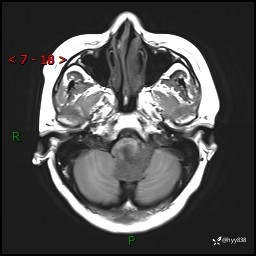

病例中年女性,头晕1年余。看看什么是软,什么是见缝钻---结果公布~

性别:女

年龄:47岁

简要病史:头晕1年余,间断恶心不伴呕吐

颅脑MRI平扫+DWI

增强(axi+cor+sag)